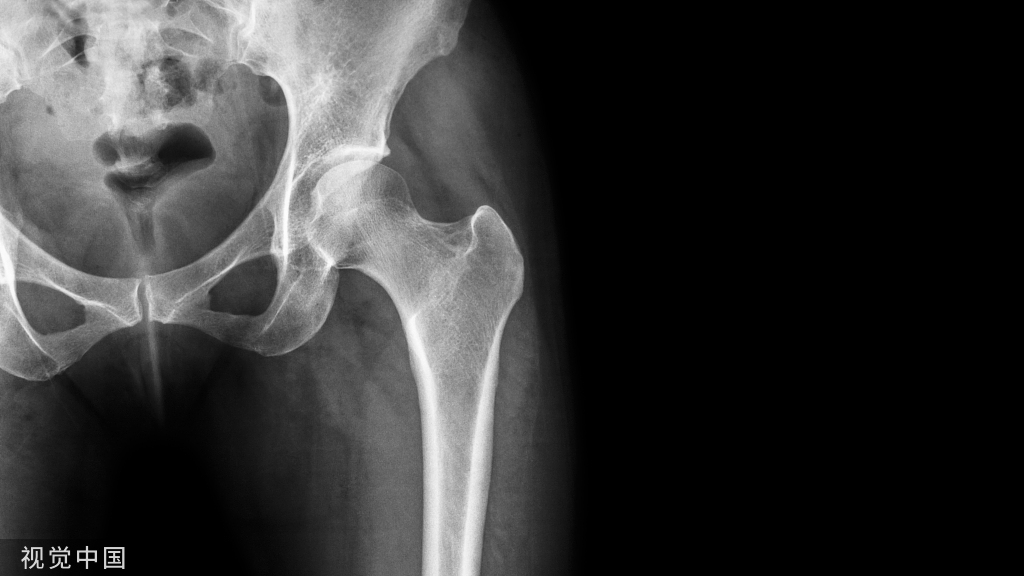

全关节置换术患者的外展肌功能不全是一个常见但具有挑战性的问题,可导致疼痛、跛行、假体磨损增加和不稳定。外展肌缺陷可继发于创伤性或磨损性撕裂、初次和翻修时的断裂、大转子的骨质丢失或骨折、肌肉萎缩、神经损伤、异位骨化以及对金属碎片的不良反应。全髋关节置换术后外展肌功能不全的发生率为0.08%-20%。

病例1:患者男,62岁,在多次左髋关节手术后,主诉左髋关节疼痛和外展肌无力。他在9年前接受了左侧全髋关节置换术,随后分别在手术后3、6和9年进行了外展肌修复术。在体检中,注意到有Trendelenburg步态。

(A-C)术前X光显示左侧股骨近端骨量减少,翻修时预先放置的模块化骨干接合股骨柄用于假体周围骨折的治疗。(D和E)在外展肌重建前进行的MRI图像显示臀中肌和小肌脂肪萎缩,股骨肌腱附着处改变。(F和G)外展肌重建18个月后的部分MRI图像显示臀中肌附着完整,臀小肌部分连续。患者报告的外展肌重建术23个月的结果包括:静息疼痛,1/10;行走疼痛,3/10;Harris髋关节评分,61;牛津髋关节评分,22。患者报告中度跛行,仅需长时间步行时需要拐杖。

病例2:一位60岁女性主诉右髋部疼痛和外展肌无力,在初次右全髋关节置换术后出现大转子骨折。2/5 外展肌肌力。

(A-C)术前X光显示大转子有轻微骨折,和先前植入的右全髋关节假体,包括非骨水泥的股骨柄和非骨水泥的髋臼假体。(D和E)在外展肌重建前进行的MRI图像显示臀中肌腱仍然附着在大转子骨折片段上。这块骨折碎片已经移位,近端移位。臀小肌腱终止于股骨近端的软组织。外展肌重建术后18个月的报告包括:休息疼痛,3/10;行走疼痛,8/10;Harris髋关节评分,26;牛津髋关节评分,37。患者报告中度跛行,行走时使用助行器。

病例3:1例81岁女性患者,左外侧髋部和腹股沟疼痛。在初次全髋关节置换术前,体检记录为Trendelenburg步态和4/5的外展肌力。MRI显示肌腱病变和累及臀中肌和臀小肌腱的部分撕裂的征象。在初次全髋关节置换术中,在股骨近端的止点发现了臀中肌和臀小肌腱部分撕裂。全髋关节假体植入后,一期缝合修复。手术后,她恢复得很好,但最终在大转子上出现了越来越多的疼痛。检查中发现3-4/5外展肌力。手术切除异位骨化。外展肌经经骨隧道进行部分修复,并通过臀大肌和阔筋膜张肌的转移来加强修复。

(A-C)术前X光显示先前植入的右侧全髋关节假体,包括非骨水泥的股骨柄和非骨水泥的髋臼假体。(D和E)外展肌重建后12个月MRI图像显示臀中肌、臀小肌、臀大重建瓣和阔筋膜张肌重建瓣完整。患者报告的外展肌重建术22个月的结果包括:静息疼痛,1/10;行走疼痛,3/10;Harris髋关节评分,58;牛津髋关节评分,23。病人报告说,走路时有轻微的跛行和拐杖。